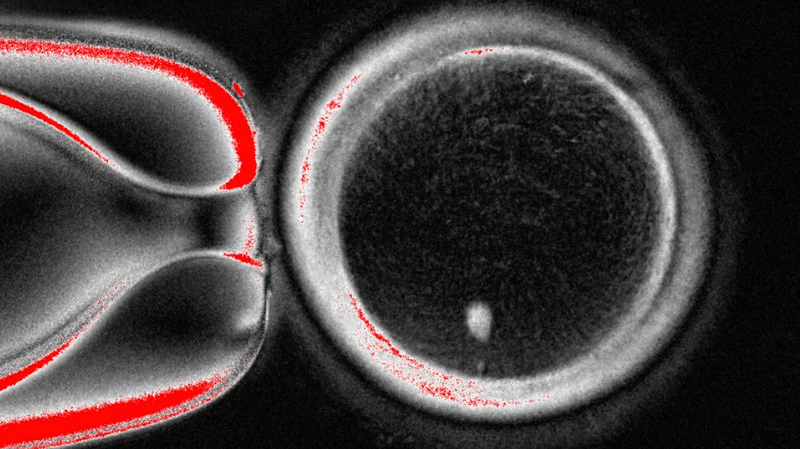

In their experiments, they created 82 of these lab eggs and fertilized them with sperm. About 9% made it to the blastocyst stage (that's a 70-200 cell embryo, the kind used in IVF). Most got stuck earlier, and some showed DNA hiccups, so the team isn't popping champagne just yet.